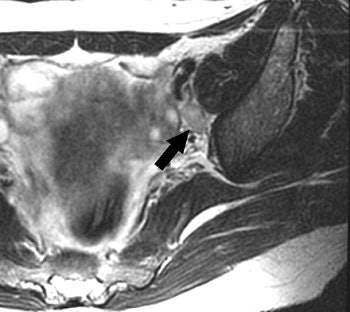

| Same patient as above. Gadolinium-enhanced axial T1-weighted turbo spin-echo sequence image (175/4.2; echo-train length, 3) shows homogeneous enhancement of left internal iliac lymph node (arrow). Histopathology showed one positive node in left internal iliac and obturator area of four nodes sampled. Choi HJ, Kim SH, Seo S, Kang S, Lee S, Kim JY, Kim YH, Lee JS, Chung HH, Lee JH Park SY. "MRI for Pretreatment Lymph Node Staging in Uterine Cervical Cancer" (AJR 2006; 187:W538-W543). |

Other reliable indicators of lymph node status on MR were a lobulated or spiculated border (21% sensitivity and 46.4% positive predictive value). These margins could be caused by a "desmoplastic reaction or tumor infiltration into the perinodal fat." However, heterogeneous enhancement patterns were not as useful for distinguishing metastatic from nonmetastatic lesions, they added.

The group ultimately concluded that despite MRI's low sensitivity, size and margin were useful criteria for predicting lymph node metastasis in cervical cancer patients. But they did caution that size and margins can overlap in metastatic and nonmetastatic lesions.